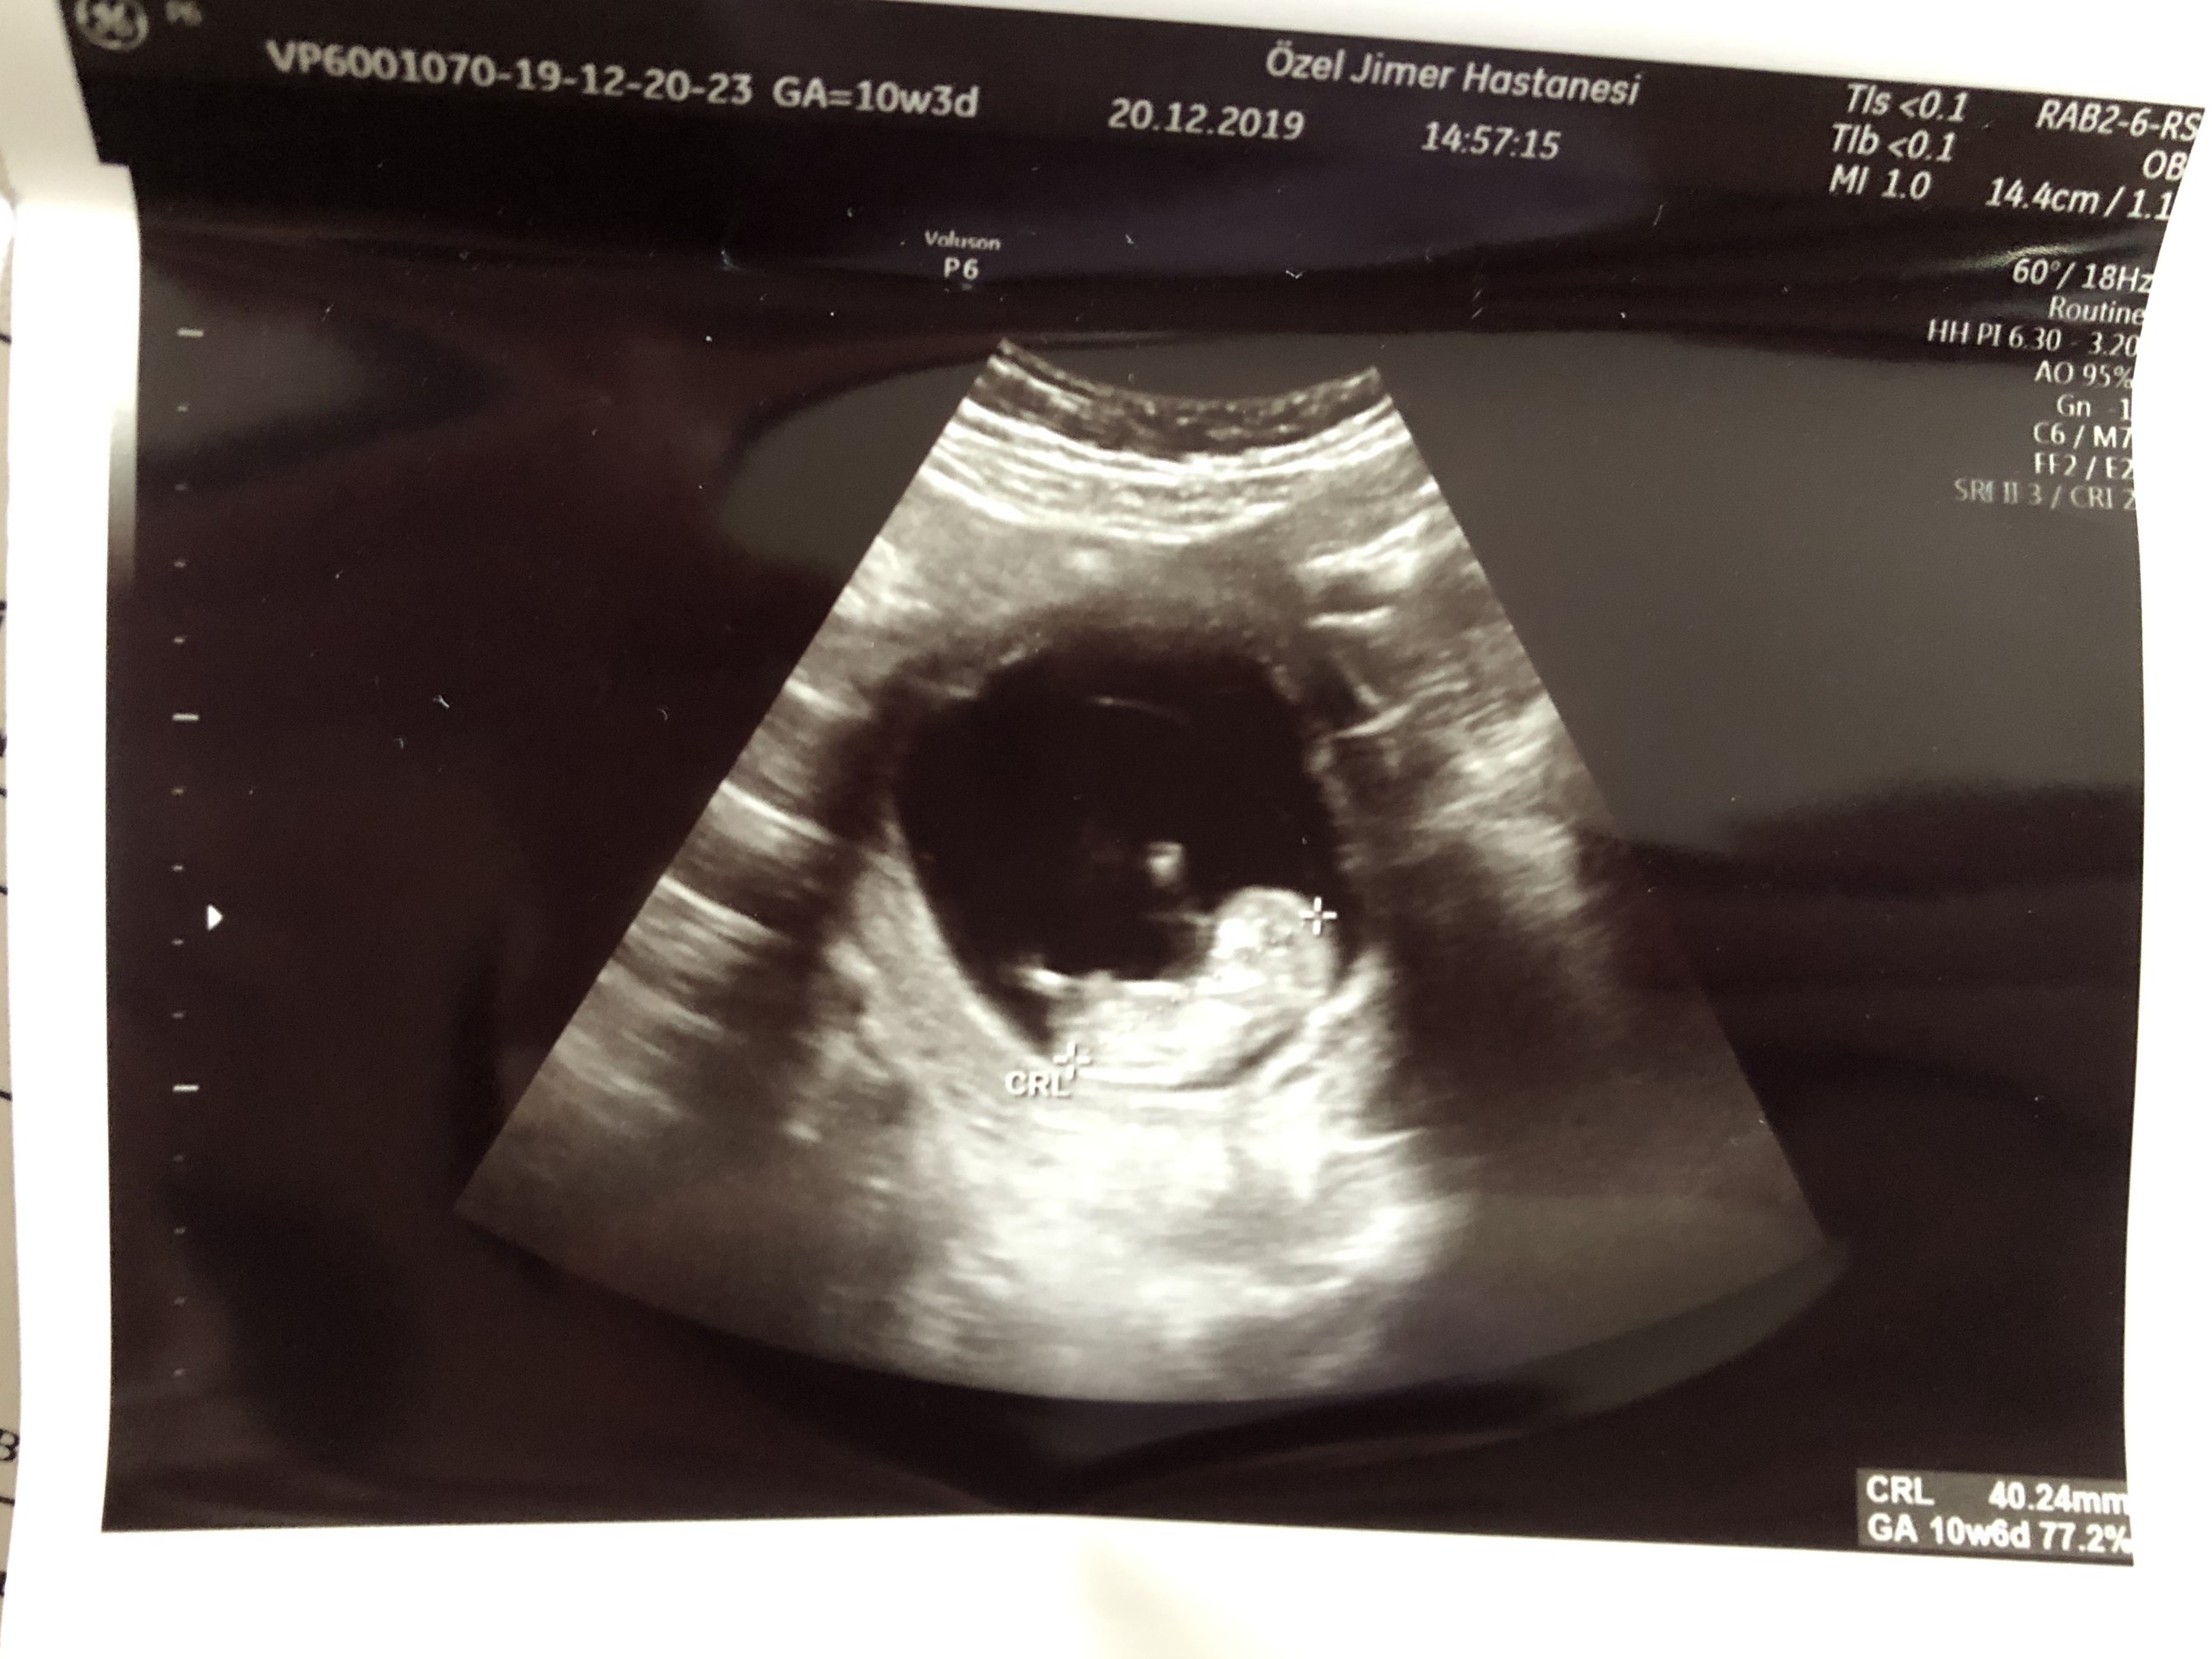

B berivannak Yeni Üye Üye 20 Aralık 2019 #681 malesef başka yok haftaya yenisini alınca atarım inşallah teşekkürler

SadmiN ♥ Evli Mutlu Çocuklu ♥ Yönetici 20 Aralık 2019 #683 Malesef ilgili bölüm çok net değil yanlış bi tahminde de bulunmak istemiyorum cepten yakın çekip gönderebilir misiniz bi kaç tane çekin atın lütfen.

Malesef ilgili bölüm çok net değil yanlış bi tahminde de bulunmak istemiyorum cepten yakın çekip gönderebilir misiniz bi kaç tane çekin atın lütfen.

SadmiN ♥ Evli Mutlu Çocuklu ♥ Yönetici 20 Aralık 2019 #685 Yani çok net olmamakla birlikte erkek diyebileceğimi düşünüyorum.